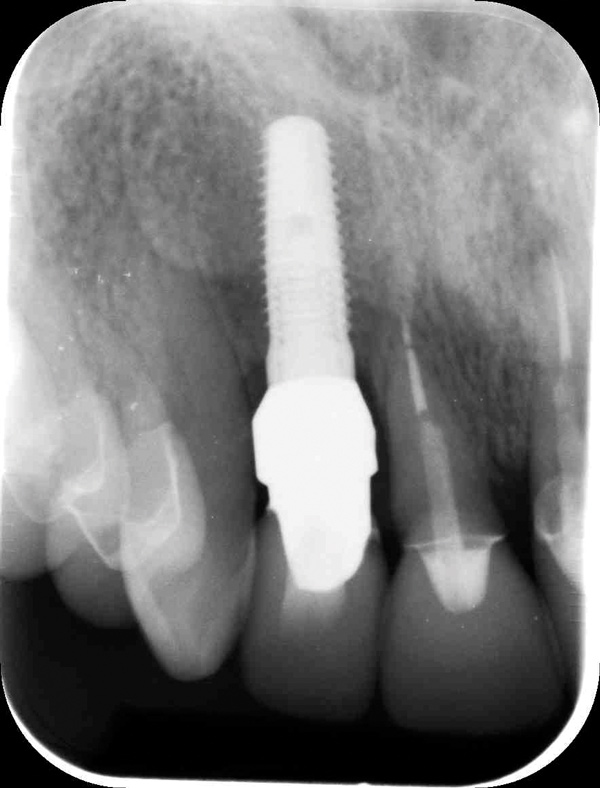

Fig 12. Final periapical x-ray showing excellent bone level and implant positioning.

Figure 12

When placing an implant in the esthetic zone, ideal 3-dimensional positioning, including mesio-distal, apico-coronal, and orofacial dimensions, is essential to achieve favorable esthetic outcomes, regardless of the implant system used (Figure 6).45 With respect to the orofacial dimension, implants should be placed in a more palatal or lingual position to allow the presence of at least 2 mm of buccal bone thickness from the implant buccal shoulder.45,46 When the distance of the buccal bone wall and implant buccal shoulder is < 2 mm, a significantly higher incidence of midfacial recession has been previously reported.3,12 Placement of bone graft (Figure 7) and immediate restoration (Figure 8 and Figure 9) at the time of implant placement has also been suggested to increase peri-implant soft-tissue height and thickness.51 In the apico-coronal dimension, the implant head should be at least 3 mm apical to an imaginary line connecting the CEJ of the adjacent teeth and 1 mm to 2 mm apical to the interproximal and crestal bone to ensure a proper implant emergence profile and facilitate proper implant restoration (Figure 10). Regarding the horizontal implant–tooth distance, implants should be placed no closer than 1.5 mm from the adjacent root surface to minimize resorption of the interproximal alveolar crest, which causes a reduction in the papillary height.46,52

When placing multiple implants in the esthetic zone, Tarnow et al reported a lower height of the bone crest in areas with an inter-implant distance of ≤ 3 mm compared with areas with > 3 mm between the implants and suggested that this difference may be the result of lateral bone loss at the implants.53 Finally, management of subgingival abutment contour and definitive crown restoration shape that is harmonious with the surrounding periodontium is needed to maintain long-term soft-tissue health and stability (Figure 11 and Figure 12).